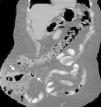

La hernia de Spiegel es un defecto en la unión del borde lateral del músculo recto del abdomen y el borde medial del transverso del abdomen. Adriaan van den Spiegel (1578- 1625) describió la línea semilunar que ahora lleva su nombre, así como su relación con el borde lateral del músculo recto abdominal (fascia de Spiegel). Eventualmente, el cirujano se enfrenta a las llamadas «hernias raras», denominadas así por su baja incidencia y su inusual contenido. Dentro de estas se incluyen las hernias de Petit, Grynfeltt, Busoga, Richter, Spiegel, Bullhorn, Handlebar, Romberg, Littre, Amyand y Garengeot. La hernia de Spiegel representa del 1 al 2% de todas las hernias; su contenido más frecuente es el intestino delgado y el epiplón. El apéndice cecal dentro del saco herniario ha sido poco descrito hasta el momento. Femenino de 63 años con antecedente de obesidad mórbida y plastia ventral con malla por hernia de Spiegel con recidiva desde hace 2 años. Ingresada a nuestro servicio por hernia de pared complicada. El topograma mostró hernia ventral y probable absceso de pared (fig. 1). La tomografía reveló apendicitis aguda complicada dentro del saco herniario (figs. 2 y 3). Durante la cirugía se identificó hernia de Spiegel recidivante complicada, saco herniario con apéndice cecal perforado con absceso de 300ml y fascitis necrosante de la pared abdominal. Se realizó drenaje de absceso, desbridación de tejido, retiro de malla previa, apendicetomía, plastia de pared sin malla y colocación de sistema de cierre asistido por vacío durante 2 semanas. La evolución posquirúrgica fue adecuada.